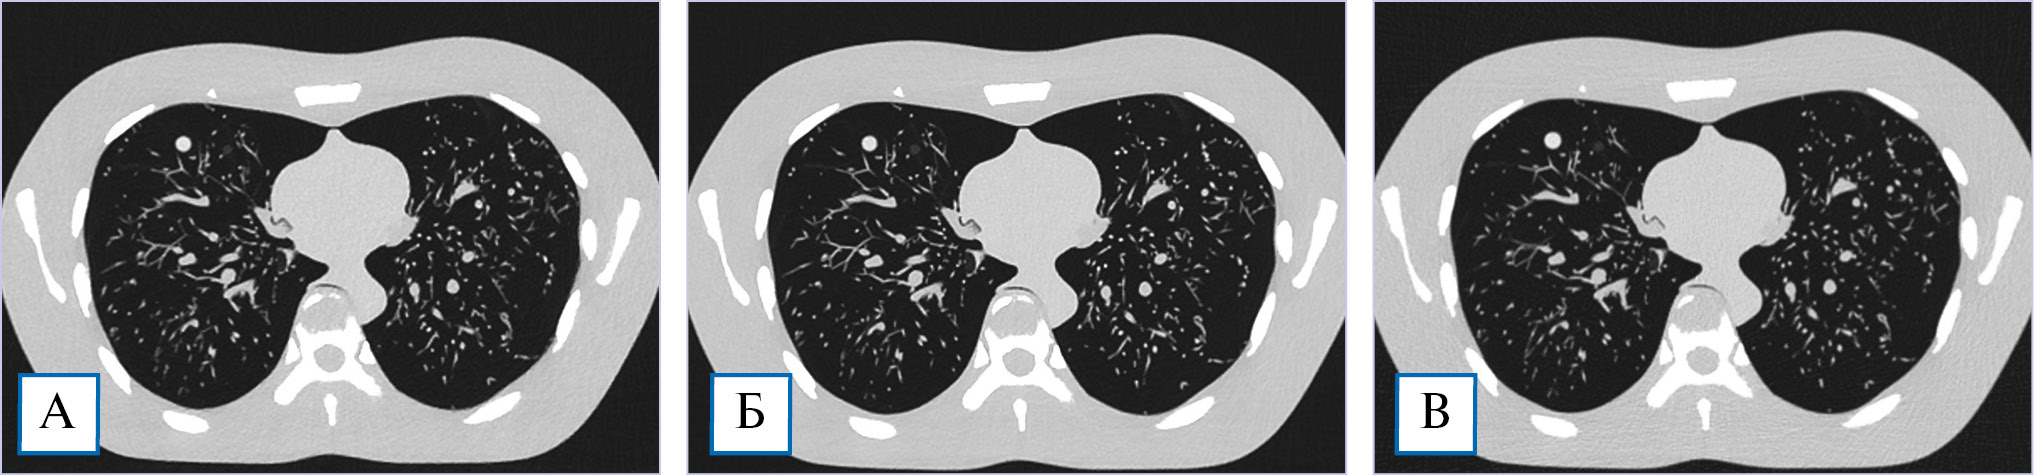

Визуальных различий качества изображения легочных структур нами не обнаружено (рис. 2). Заданные очаги были выявлены при всех методах реконструкций.

Рис. 2. Компьютерно-томографические изображения антропоморфного фантома в легочном окне: А — модельная итеративная реконструкция при низкой дозе облучения; Б — стандартная компьютерная томография с модельной итеративной реконструкцией; В — стандартная компьютерная томография с гибридной итеративной реконструкцией.